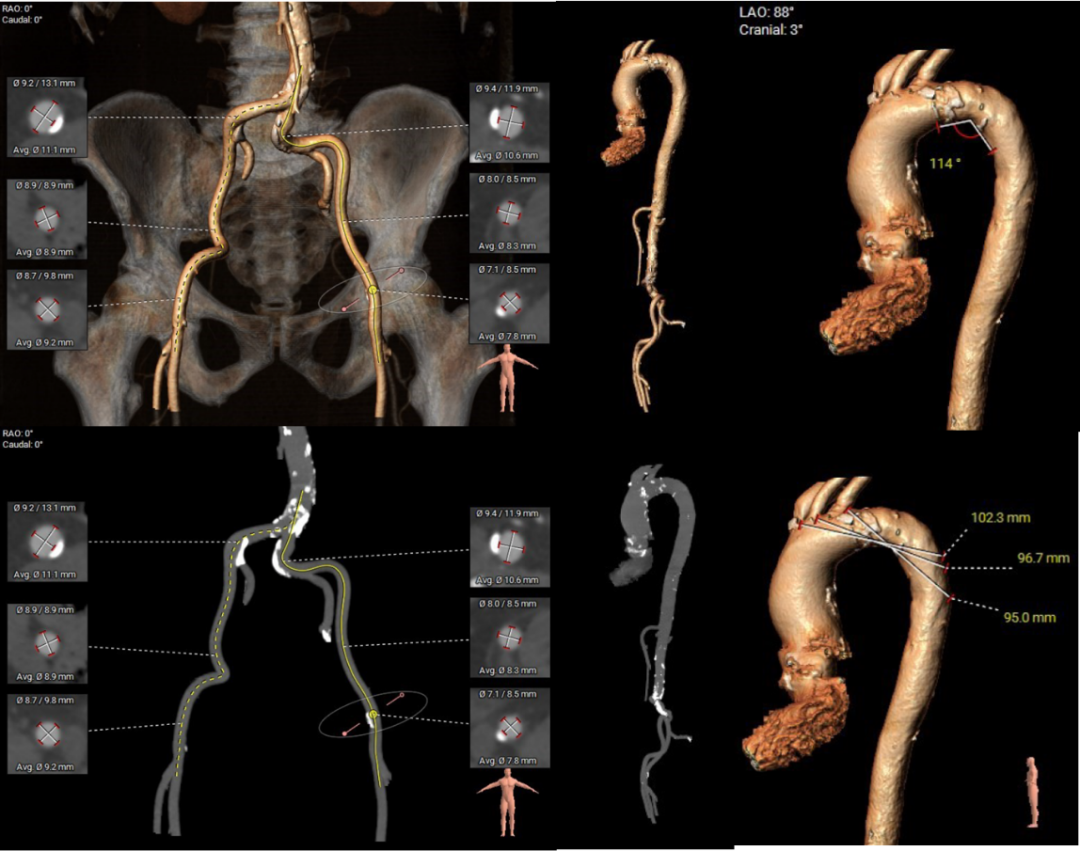

主动脉根部评估:

三叶式主动脉瓣,瓣环周长78.4mm,平均周长径24.9mm,左冠脉开口高度大于瓣叶长度,综合考虑冠脉风险低,LVOT周长径24.9mm,升主动脉直径30.8mm。

左冠高度17.5mm右冠高度22.6mm,右冠脉开口高度大于瓣叶长度,SOV瓦式窦:平均周长径38.2mm,术中仍球囊预扩须密切注意冠脉灌注,STJ周长径29.4mm。

瓣叶重度钙化伴增厚,钙化分布不均匀,HU596积分930mm²。

左室腔内径偏小,心室壁增厚明显。

主动脉弓角度与宽度可,心脏水平夹角53°,非横位心,外周血管内散见钙化灶,双侧入路血管内径良好,整体入路血管条件较好。